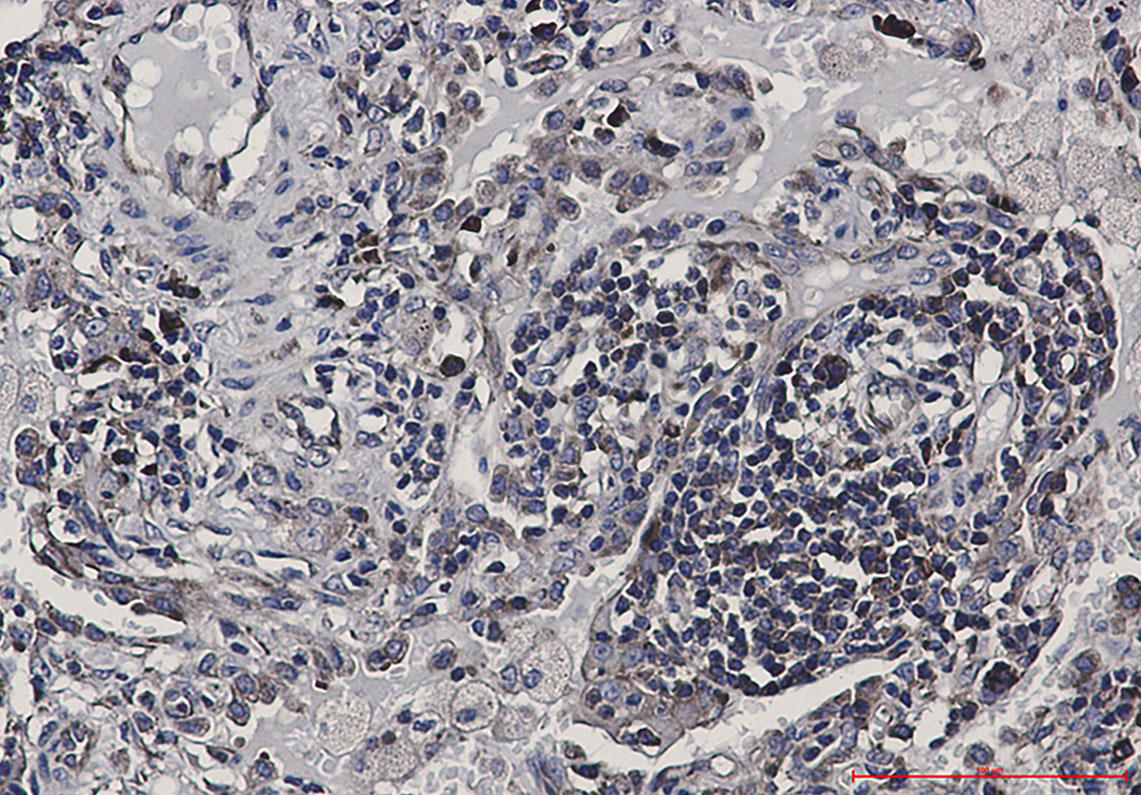

Immunohistochemistry analysis of paraffin-embedded Human lung cancer using eIF4B antibody.High-pressure and temperature Sodium Citrate pH 6.0 was used for antigen retrieval.